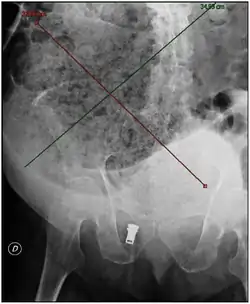

![]() تظهر الأشعة السينية للبطن انحرافًا برازيًا ضخمًا يمتد من الحوض لأعلى إلى المساحة السفلية اليسرى، ومن اليسار نحو الجهة اليمنى ويبلغ طوله 40 سم وعرضه 33 سم. تظهر الأشعة السينية للبطن انحرافًا برازيًا ضخمًا يمتد من الحوض لأعلى إلى المساحة السفلية اليسرى، ومن اليسار نحو الجهة اليمنى ويبلغ طوله 40 سم وعرضه 33 سم. | |